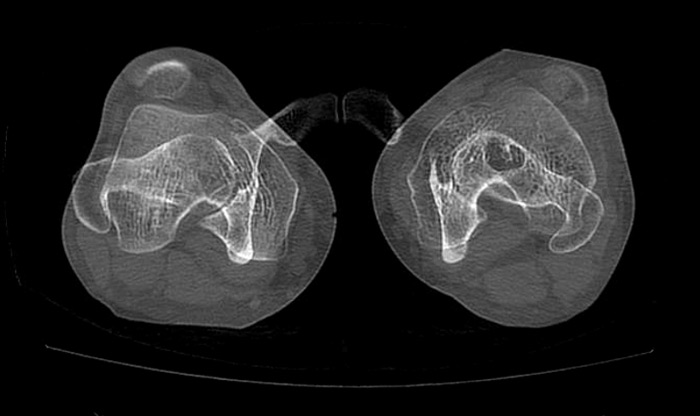

Pre-operative CT-scan

Pre op CT-scan

Pre-operative measurements

• HKA = 180°

• TT-TG = 24 mm

• Femoral neck anteversion (FNA) = 27.5°

• Dejour type C trochlear dysplasia